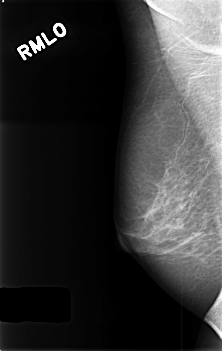

C_0406_1.RIGHT_MLO

RIGHT_MLO LINES 4560 PIXELS_PER_LINE 2880 BITS_PER_PIXEL 12 RESOLUTION 50 NON_OVERLAY